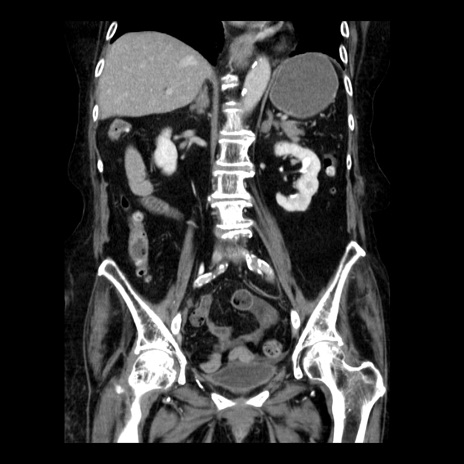

横断像

【症例】 90歳代女性

【主訴】 腹痛・嘔吐

【現病歴】今朝から左側腹部痛を認めた。 経過観察していたが、嘔吐を認めたため来院。

【既往歴】 子宮癌術後

【身体所見】 意識清明、BP 127/54mmHg、P 98bpm Sp02 95%(RA)、BT 35.8°C、腹部平坦・軟腸ぜん動音聴取良好、右下腹部圧痛(+) 反跳痛なし

【データ】WBC 9800、CRP 0.46